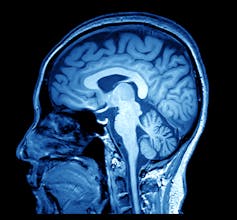

However, it turns out that the single biggest use of helium is to support our medical imaging industry, specifically magnetic resonance imaging or MRI, and high-end material analytics that take advantage of very high magnetic fields to make the nuclear magnetic resonance, or NMR, spectroscopy measurements. Those fields would not be possible to generate without liquid helium’s ultra-low boiling point.

The key to the MRI and NMR devices, which are used to image the human body, is the use of superconducting materials that are stable at 4.2 K. Most materials resist the flow of electrons, or current, through them and this turns out to be a problem for magnet construction. Every single electronic device we use, every single wire feeding current to wall outlets, and all the infrastructure used to transport electrical energy through the grid waste energy through resistive forces. This resistance makes it difficult to generate a large magnetic field with high electrical currents required. A superconductor is magical, almost, and has no resistance to the flow of electrons and has the capacity to generate an enormous magnetic field, enabling high-resolution medical imaging. But for a superconductor to function correctly it must be kept at ultra-low temperatures – which is where liquid helium is essential.